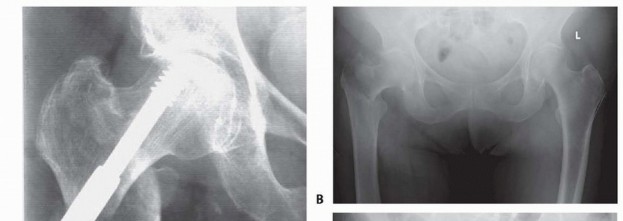

POSTOPERATIVE CARE 413 AP and lateral radiographs of the operative hip should be obtained immediately postoperatively in the recovery room to assess implant position and fracture reduction and to ensure that no iatrogenic femur fracture was produced intraoperatively. The entire device should be included in the radiograph ( FIG 6). Patients are mobilized as soon as their cardiopulmonary and mental status will safely allow, usually by postoperative day 1. Unrestricted immediate postoperative weight bearing is easiest for the patient to comply with, and multiple investigations have shown no increase in fixation failure as a result of this postoperative rehabilitation protocol. 8 Koval et al 7 used gait analysis to show how patients effectively autoregulate their weight bearing postoperatively, with the patients who had the least stable fracture patterns preoperatively putting the least amount of weight on their legs immediately postoperatively. Patients should be seen 2 weeks postoperatively to check for uneventful wound healing. Follow-up radiographs should be obtained at 2, 6, and 12 weeks to check for controlled fracture impaction, exclude any fixation device complications, and assess fracture healing. ## OUTCOMES With proper fracture reduction, implant selection, and fixation device positioning, peritrochanteric hip fractures heal in up to 98% of cases. One-year mortality rates after fixation of peritrochanteric hip fractures range from 7% to 27%, with most studies finding a rate of 15% to 20%. 11 According to Medicare data, 30-day and 180-day mortality rates continue to improve. Mortality rates depend on both preoperative and postoperative medical complications and condition as well as preoperative functional status. Postoperative functional status also depends on numerous variables: Socioenvironmental functional status has been shown to be of great importance in determining the postoperative function status of a patient. 11 ### FIG 6 • Postoperative AP (A) and lateral (B) radiographs showing correct implant positioning and no intraoperative complications. Longitudinal studies comparing the functional status of patients before and after hip fracture fixation have documented that roughly 40% of patients maintain their preoperative level of ambulation postoperatively. Another 40% of patients have increased dependency on ambulation devices but remain ambulatory. Twelve percent of patients become household-only ambulators, and 8% of patients become nonambulators postoperatively. 6

COMPLICATIONS Loss of proximal fixation is defined as varus collapse of the proximal fracture fragment with cutout of the lag screw from the femoral head ( FIG 7A). This complication is seen in 4% to 20% of fractures, usually within 4 months of surgery. Although certain fracture patterns have been shown to have a higher rate of proximal fixation loss, the fracture pattern cannot be controlled by the physician. The placement of the lag screw, on the other hand, can be controlled by the physician. A central and deep position with a tip-apex distance of less than 25 mm has been shown to significantly reduce the incidence of proximal fixation loss. 2 Nonunion occurs in 1% to 2% of fractures. The low incidence is likely due to the well-vascularized nature of the cancellous peritrochanteric region of the hip through which these fractures develo Secondary fracture displacement Despite adequate fracture reduction and implant positioning, fractures may progress to excessive impaction, with resultant limb shortening and abductor weakening ( FIG 7B,C). This can lead to suboptimal patient functional results. This is often seen in cases of unrecognized lateral wall fractures (either iatrogenically induced by implant placement or unrecognized from the original trauma). Use of intramedullary fixation devices and vigilant followup may help avoid this complication. Infection Wound dehiscence 414 ### FIG 7 • A. Varus collapse. B. AO/OTA type 31-A1 peritrochanteric hip fracture fixed with a sliding hip screw. C. Followup radiograph 6 months postoperatively showing secondary fracture displacement.